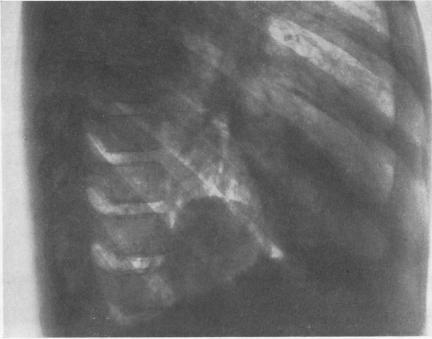

Fifty-seven cases of diaphragmatic hernia and eventration.

Thorax. 1950 Dec;5(4):343-61. doi: 10.1136/thx.5.4.343.